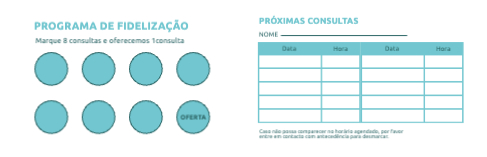

Escolher um template (Cartões de Visita com Dobra)

VoltarModelos de Cartões de Visita com Dobra

Explore diferentes estilos e modelos de cartões de visita com dobra. Escolha o design que melhor representa o seu negócio e personalize-o facilmente no nosso editor de design online.